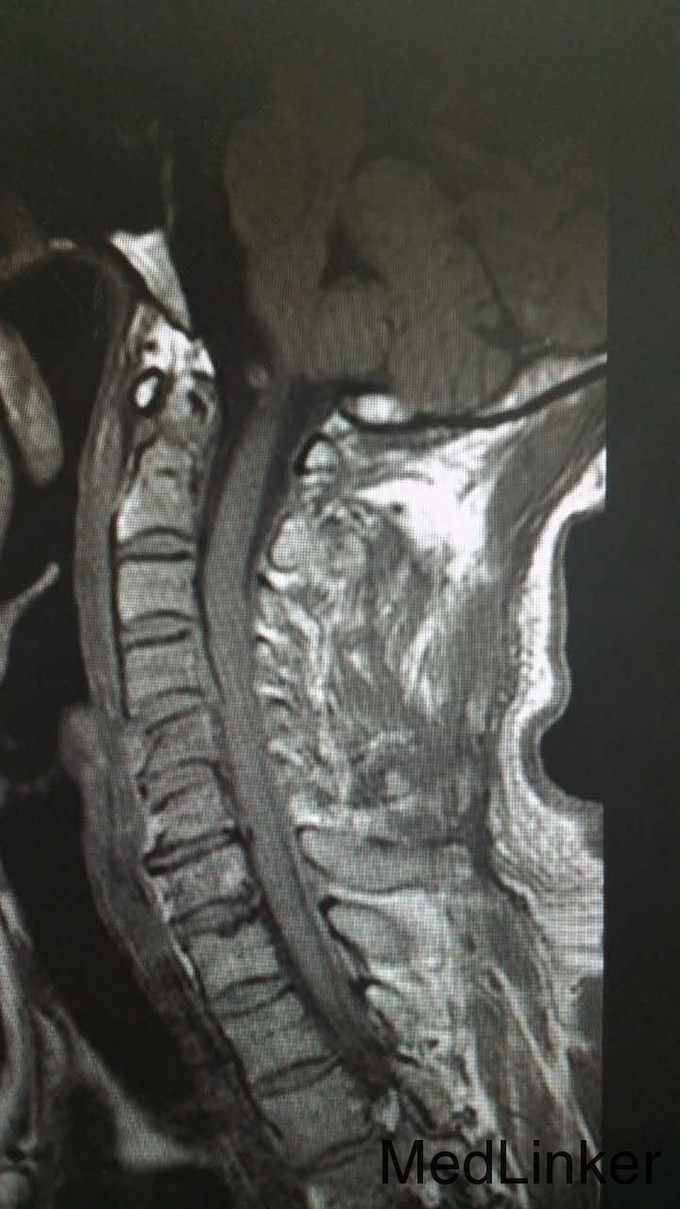

查体:T4平面以下痛觉消失,四肢肌力0级。双侧病理征阳性。 辅检:全身CT示:C4左侧椎扳、侧块、C5-6左侧横突多发骨折,C5椎体压缩骨折,C4椎体滑脱,颅内未见明显血肿,胸腹盆末见明显外伤行病变。头颅MRI示:C3-6水平颈髓出血伴水肿。

诊断:1.C3-6水平颈髓损伤出血伴水肿,2.C4左侧椎扳、侧块、C5-6左侧横突多发骨折,3.C5椎体压缩骨折,4.C4椎体滑脱(Ⅰ度) 治疗:伤后5天,予行C3-6椎板切除、椎管减压,侧块固定融合术

随访:现术后10天,患者右上肢肌力4级,右下肢肌力1-2级,左上肢肌力1级,左下肢肌力0级。 讨论:患者颈椎脊髓损伤,脊髓出血伴水肿,局部压力高,行减压后缓解局部压力,有助于脊髓功能恢复。